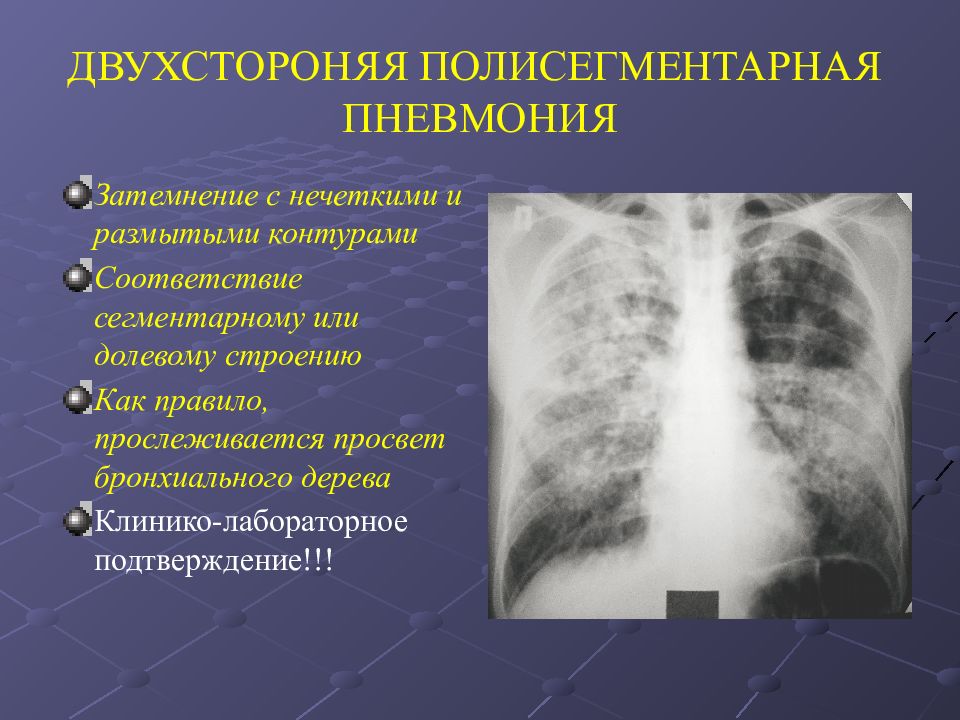

Фотографии, демонстрирующие обнаруженное усиление легочного рисунка

Раздел: Фотодневник открытий